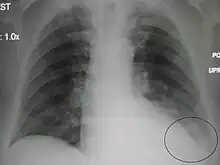

Right upper lobe pneumonia as marked by the circle.